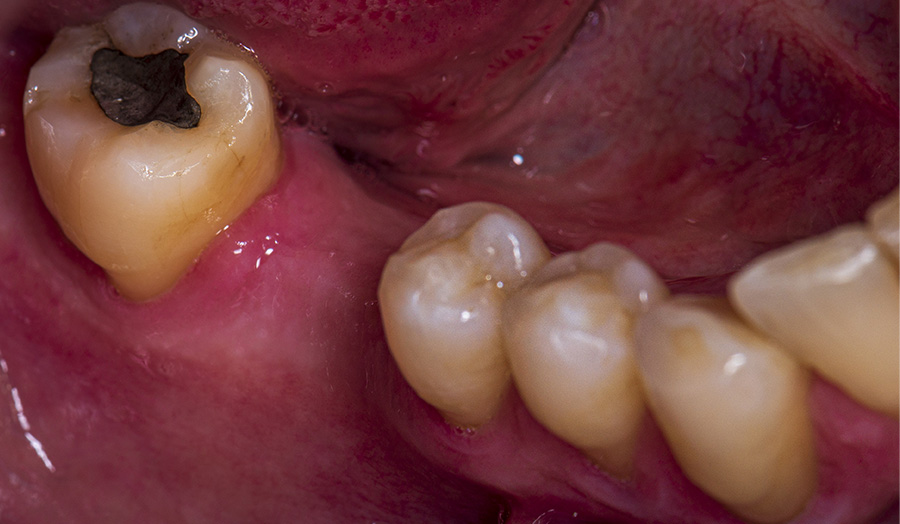

A 58-year-old male patient presented himself to my practice with a missing tooth #30 to restore the natural chewing function while preserving healthy tooth structure. The gap was to be restored with an implant and a ceramic crown. I planned and implemented the treatment digitally.

Before: Initial oral situation of missing tooth